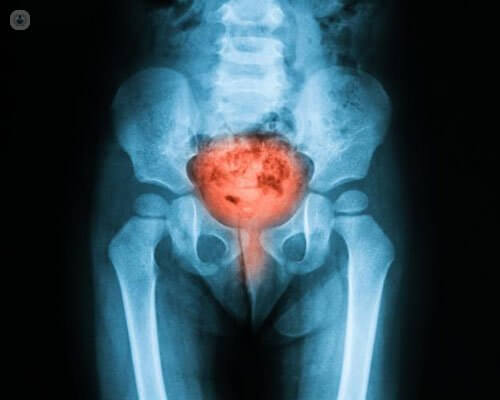

التهاب مثانه

التهاب مثانه نوعی عفونت مجاری ادراری است که معمولا برای خانم ها ایجاد میشود و بیشتر از اینکه نگرانی برای سلامتی ایجاد کند، باعث درد و آزار میشود. موارد خفیف این بیماری اغلب بصورت خود به خود بعد از چند روز بهبود میابد. با این حال، برخی از افراد که به طور مکرر عفونت و التهاب مثانه را تجربه می کنند، ممکن است به درمان منظم یا طولانی مدت نیاز داشته باشند.

همچنین این احتمال وجود دارد که التهاب مثانه در برخی موارد منجر به عفونت جدی تری در کلیه شود، بنابراین در صورت عدم بهبود علائم مهم است که به مشاوره تخصصی مراجعه کنید.